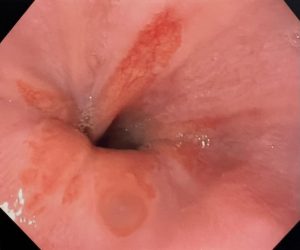

Cuando usted come, el alimento pasa desde la garganta al estómago a través del esófago. Un anillo de fibras musculares en la parte inferior del esófago impide que los contenidos estomacales se devuelvan.

Si estos músculos no se cierran herméticamente, se puede filtrar un ácido áspero hacia el esófago. Esto se denomina reflujo o reflujo gastroesofágico (ERGE, enfermedad de reflujo gastroesofágico). Con el tiempo, esto puede causar daño tisular. El revestimiento se vuelve similar al del estómago.